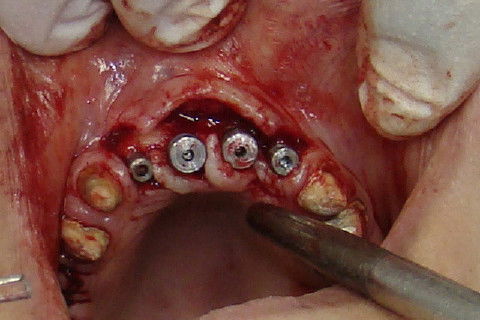

Colocação dos implantes nas regiões 12 e 22 e perfuração das regiões 11 e 21

Vista oclusal dos 4 implantes colocados